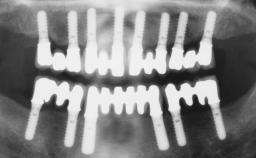

Immediate Loading of Six Implants in the Maxilla and Final Restoration with a Full-Arch CAD/CAM Zirconia FDP

A 63-year-old male patient was referred for a consultation and treatment of partial edentulism in the maxilla. The patient presented with residual anterior teeth and declined a partial removable prosthesis. He reported that the maxillary posterior teeth had been extracted due to mobility and periodontal disease two months before the consultation. The patient’s chief complaint was that his residual maxillary teeth were mobile and that he was unable to chew. The patient’s desire was a stable and comfortable fixed maxillary rehabilitation. The patient was a light smoker (fewer than 10 cigarettes/ day), and his medical history was without significant findings. He was not on any regular medication at the time of consultation. The extraoral examination revealed a normal physiognomy with a correct distribution of the facial thirds. The patient presented a low lip line, and the transition line between teeth and soft tissues was not exposed during a forced smile.

# of Implants 6

Type of Implants One-Piece

Defining Characteristics Fully edentulous upper jaw to be rehabilitated with four or more implants

Modality 6+ implants with immediate loading